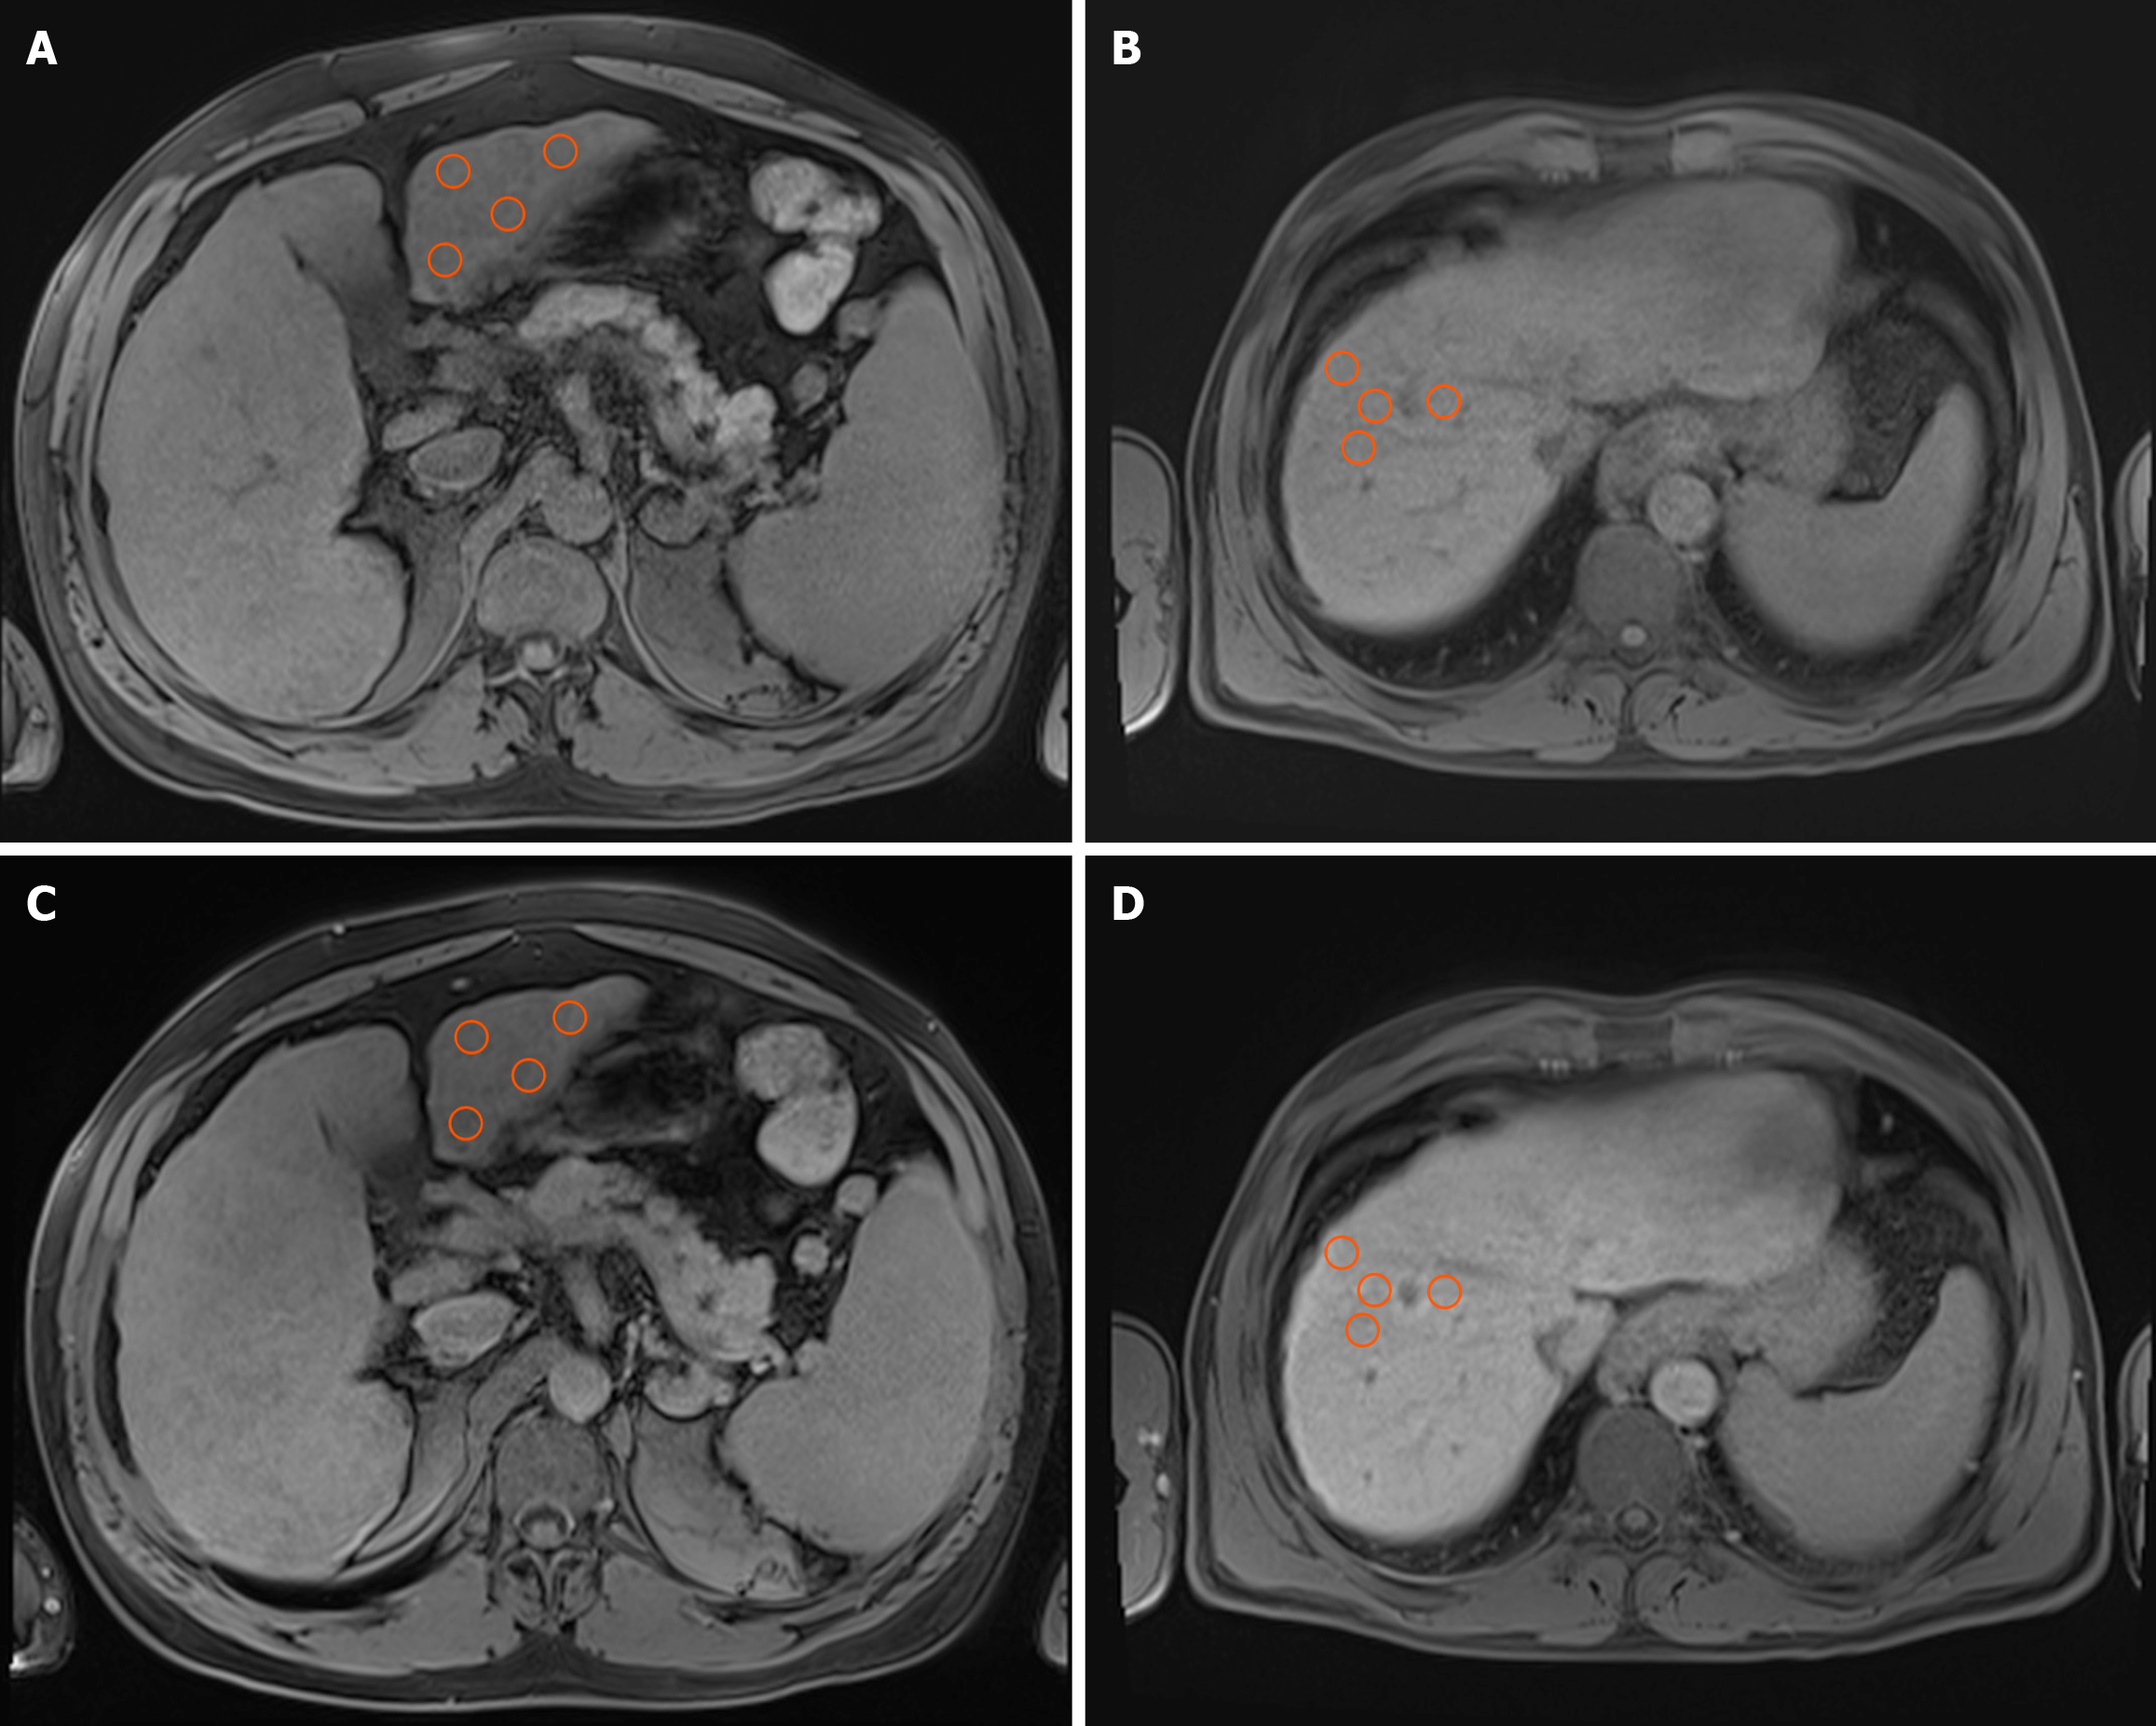

SI measurements were conducted utilizing the built-in tools of the viewer three-dimensional pro application within the PixelData picture archiving and communication system. Circular regions of interest (ROIs), each with a standardized area of 1 cm2, were manually positioned within the hepatic parenchyma. The software automatically computed SI values as the mean of all pixel intensities within each ROI. To ensure precision, ROIs were exclusively placed in homogeneous regions of the liver parenchyma, deliberately avoiding vascular structures, bile ducts, and focal lesions such as HCC, regenerative nodules, or vascular malformations.

The liver was divided into eight anatomical segments following the Couinaud classification. Segments III, VI, VIII, and I (caudate lobe) were chosen for analysis to cover both hepatic lobes, anterior and posterior territories, and the caudate lobe. This selection aimed to maximize the representation of regional functional differences while allowing consistent ROI placement in parenchyma that is relatively free of large vessels, bile ducts, or artifacts. Although direct evidence for segment-specific perfusion differences is limited, recent studies suggest that these regions show greater perfusion heterogeneity in portal hypertension, justifying the inclusion of multiple vascular territories[26].

To reduce potential variability from manual ROI placement, ROIs were positioned using standardized coordinates based on vascular landmarks (with the portal vein bifurcation as the reference point), following recommendations for reproducibility in radiomics modeling[27]. Within each chosen segment, four independent ROIs were placed, and the final SI value for each segment was determined by averaging these four individual measurements. This methodology was applied to both unenhanced (native) images and hepatobiliary-phase images (Figure 1). For each patient, SI was mea